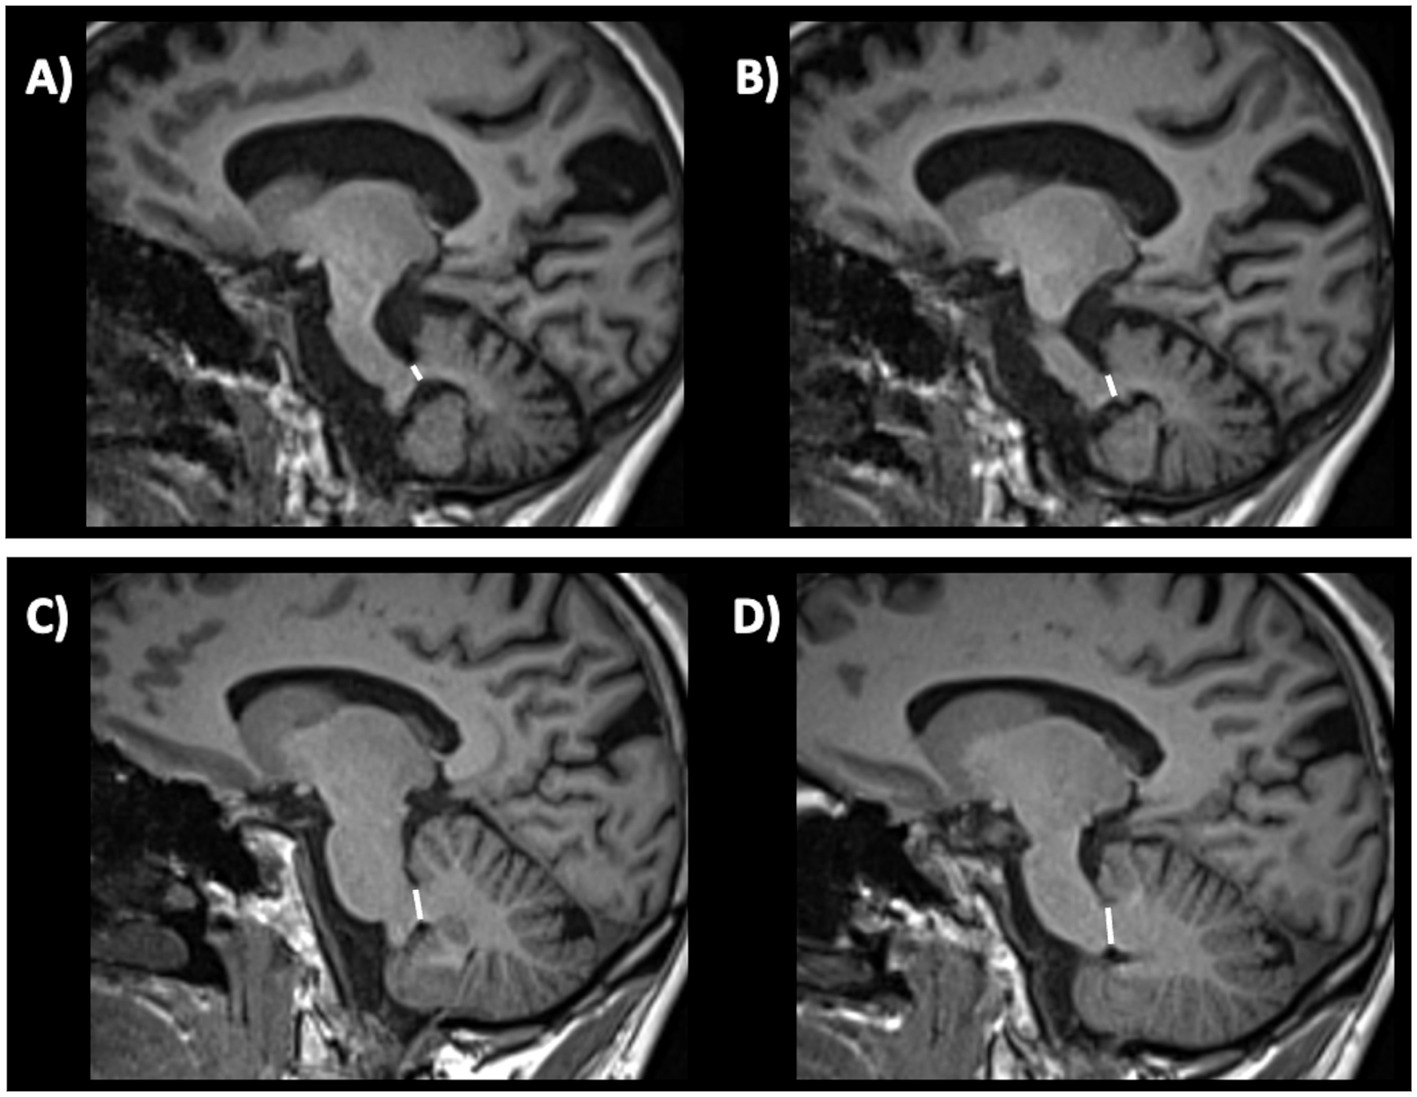

Putaminal atrophy on T1-weighted images showed a sensitivity of 83% and a specificity of 87% in distinguishing MSA-P from PD in one study (192), while other authors reported lower sensitivity, around 50% (197–199). This radiological sign, however, is not easy to evaluate and measure on MR images. Putaminal alterations such as atrophy, hypointensity and putaminal rim on T2-weigthed images May also precede clinical diagnosis in about 30% of patients with MSA-P, potentially contributing to an early diagnosis of the disease (200, 201). Putaminal atrophy and hypointensity MRI signs are shown in Figure 6.

Figure 6

Brain axial 3T-MR images showing atrophy (A) and hypointensity (B) of postero-lateral putamina in multiple system atrophy—parkinsonian type patient, and the normal putaminal appearance in a patient with Parkinson’s disease (C,D). Figures (A–C) are T2-weighted axial MR images; figures (B–D) are T2*-weighted gradient echo (T2* GRE) axial MR images.

4.1.3.2 MSA-C

In MSA-C patients, several infratentorial features such as hyperintensity or atrophy of the middle cerebellar peduncle (MCP) and atrophy of cerebellum and pons and hot-cross bun sign had strong discriminating power comparing to PD and healthy controls (192, 193, 202–204). In MSA-C, the most sensitive findings were atrophy of MCP and pontine atrophy (100%, both) (Figures 7A–D) while signal increase in the MCP and hot-cross bun showed the highest specificity (100%) (192). The hot cross bun sign (HCBs) is a cruciform configuration of hyperintensity in the pons on T2-weighted MR images attributed to degeneration of transverse pontocerebellar fibers (Figures 7E,F). Despite being a radiological hallmark for MSA (205) with high specificity (96.7%), its sensitivity is only 37–50% (192, 198). Some authors (206) investigated 81 MSA patients (50 MSA-C and 31 MSA-P) with HCBs demonstrating that the severity of this sign showed a positive linear correlation with the scale for assessment and rating of ataxia scores in MSA-C, suggesting that HCBs is a potential imaging marker for the severity of cerebellar ataxia (206). The increase in the HCBs grade was associated with an increased likelihood of disability in MSA-C, but not MSA-P cases, suggesting that it may be a useful imaging indicator for disease progression in patients with MSA-C (206). Although the HCBs is typically considered pathognomonic for MSA in the context of degenerative parkinsonian syndromes, a note of caution is needed in clinic due to the possible radiological overlap between MSA-C and other conditions, such as spinocerebellar ataxia (SCA) type 2 (207, 208). Among the different forms of SCA, HCBs is quite rare in SCA 1, 3, 6, 7, 8, while it has been consistently reported in SCA 2 (209–212), with a prevalence ranging from 10–12% in early-stage patients to around 30% of patients in later disease stages (212).

Figure 7

Brain axial 3T-MR images showing infratentorial atrophy in multiple system atrophy. Midsagittal and parasagittal T1-weighted MR images, respectively, show pons atrophy (A) and middle cerebellar peduncle atrophy (C) (highlighted by the white arrows) in a patient with MSA-C, and the normal pons and middle cerebellar peduncle appearance in a patient with PD (B–D). A T2-weighted axial MR image (E) show a cruciform hyperintensity in the pons (“hot cross bun” sign) in an MSA-C patient, and absence of this sign in a PD patient (F). MSA-C, multiple system atrophy—cerebellar type; PD, Parkinson’s disease.